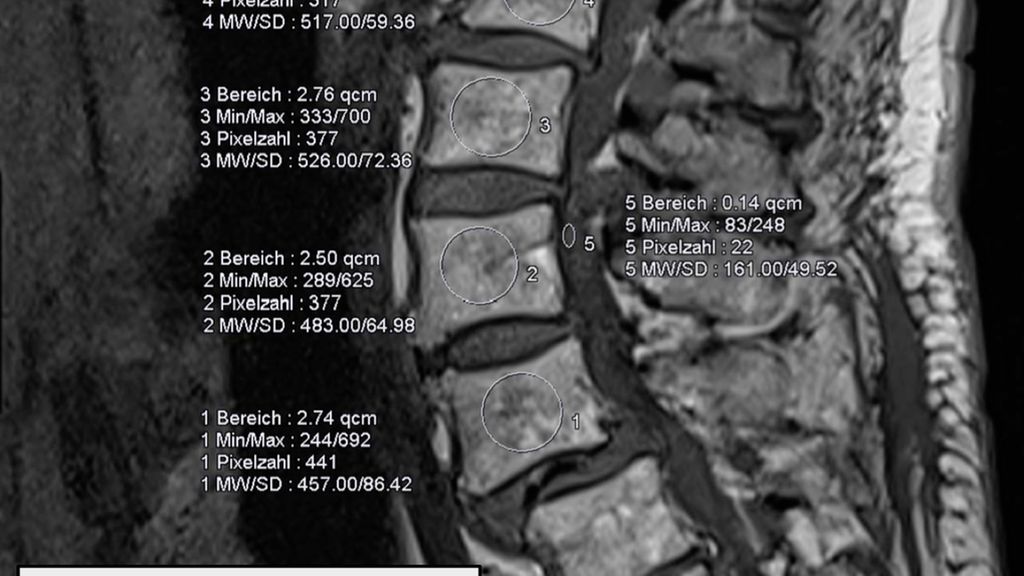

Durch den reduzierten Knochenumbau bei osteoporotischen Patient:innen kommt es auch zu einer verlangsamten knöchernen Fusion, wodurch nicht nur die Risiken für Schraubenlockerungen, sondern auch für Cage-Sinterung (Abb. 2) und Anschlussfrakturen erhöht sind.4, 21 Ein klarer Vorteil für ein bestimmtes Cage-Material dürfte nicht vorliegen. Cages aus Polyetheretherketon (PEEK) oder 3D-Druck versuchen, das Elastizitätsmodell des Wirbelkörpers zu spiegeln. Manche Studien deuten darauf hin, dass reine Titanimplantate eine höhere Sinterungsrate aufweisen als Implantate aus PEEK oder 3D-Druck.25 Viel mehr scheint die Implantatpositionierung und -größe eine Rolle zu spielen. Je mehr Kontakt zur Endplatte besteht, d.h., je größer das Implantat ist und je satter es anliegt, desto eher werden Druckspitzen vermieden und damit das Risiko für Sinterung reduziert.26

Abb. 2: Erhöhtes Risiko für Cage-Sinterung und Anschlussfrakturen durch reduzierten Knochenumbau